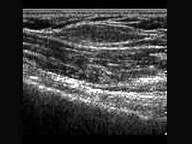

问题 患者,男,28岁,皮下扪及肿块六月余。超声检查压之不变形。声像图提示?(?)

选项 A.脂肪瘤 B.纤维瘤 C.皮下组织增厚 D.炎症 E.皮脂腺囊肿

答案 B